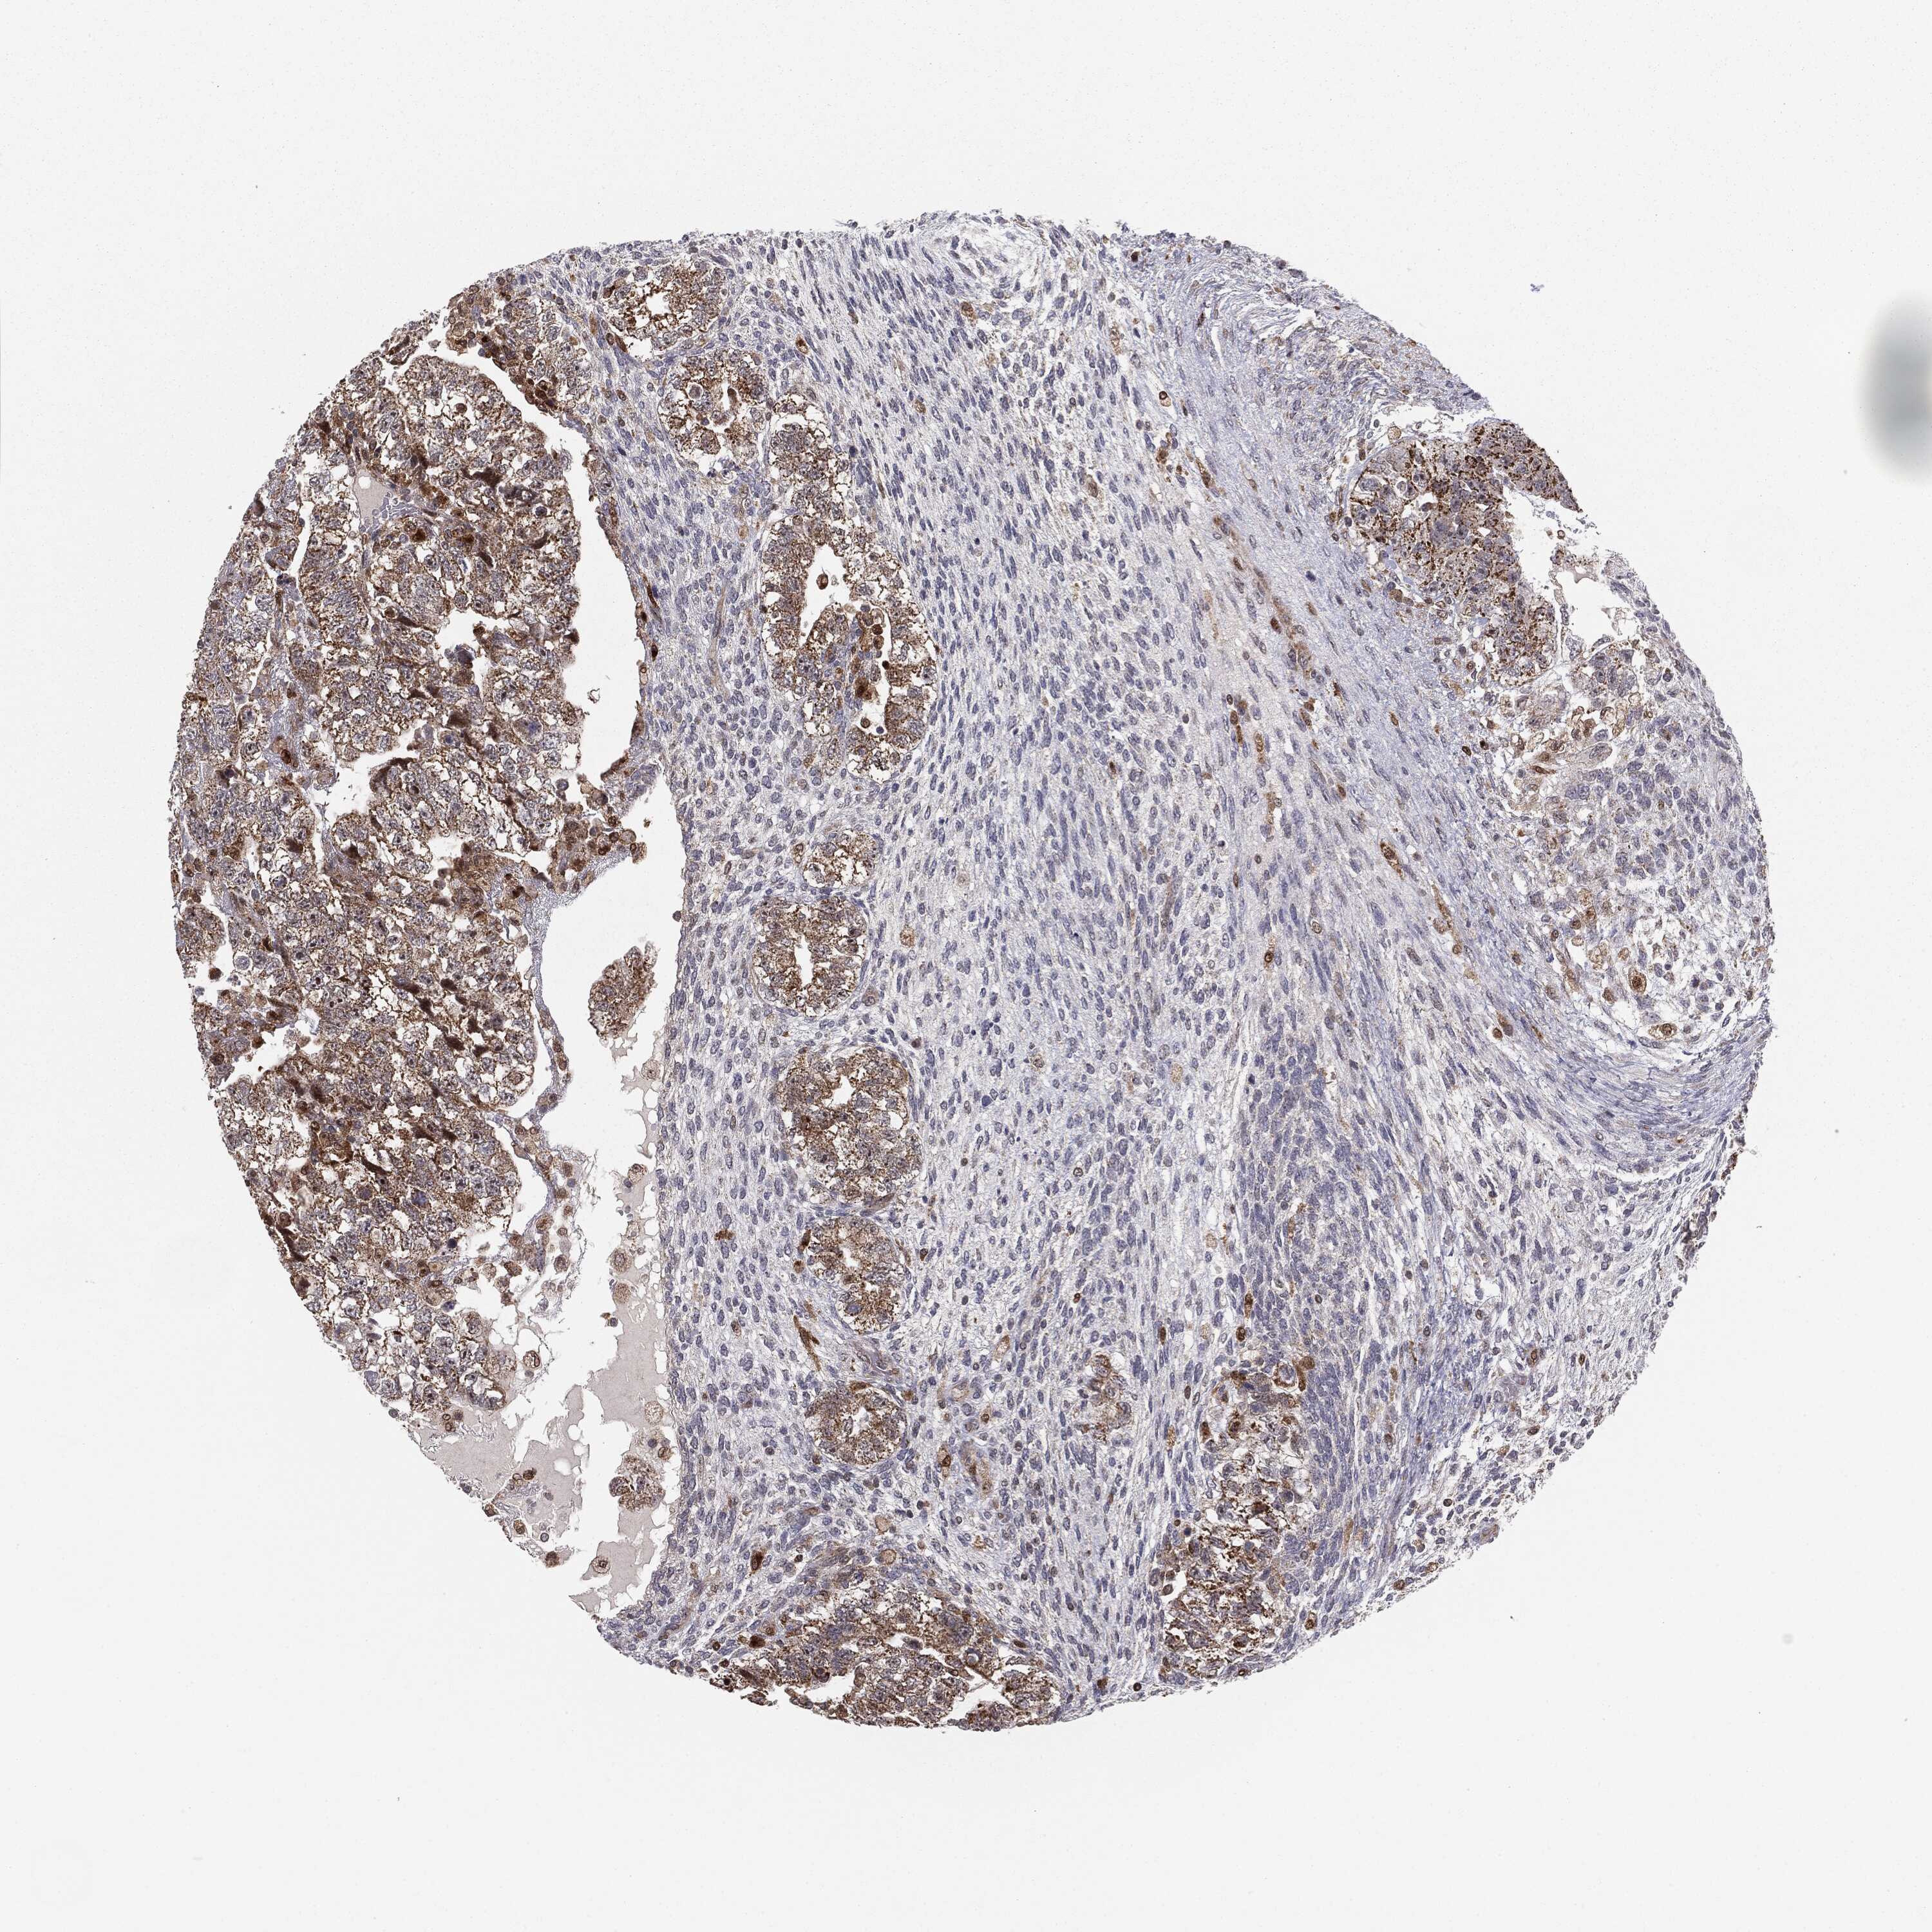

TESTIS CANCER - Protein expressioni

A mouse-over function shows sample information and annotation data. Click on an image to view it in a full screen mode. Samples can be filtered based on level of antibody staining by selecting one or several of the following categories: high, medium, low and not detected. The assay and annotation is described here.

Note that samples used for immunohistochemistry by the Human Protein Atlas do not correspond to samples in the TCGA dataset.

Antibody stainingi

Antibody staining in the annotated cell types in the current human tissue is reported as not detected, low, medium, or high, based on conventional immunohistochemistry profiling in selected tissues. This score is based on the combination of the staining intensity and fraction of stained cells.

Each image is clickable and will lead to virtual microscopy that enables deeper exploration of all samples and also displays staining intensity scores, fraction scores and subcellular localization as well as patient and tissue information for each sample.

Antibody HPA031335

Antibody CAB004076

Antibody CAB080153

Antibody CAB080157

Staining

High

Medium

Low

Not detected

Intensity

Strong

Moderate

Weak

Negative

Quantity

>75%

75%-25%

<25%

None

Location

Nuclear

Cytoplasmic/membranous

Cytoplasmic/membranous,nuclear

Seminoma, NOS

Carcinoma, Embryonal, NOS